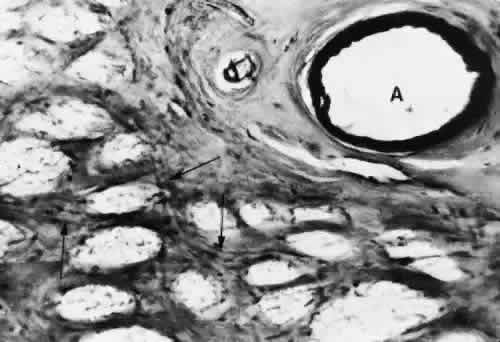

Fig. 10. Cross section of the lamina cribrosa showing fine blood vessels (arrows) traversing the trabeculae. The central retinal artery (A) is at the upper right.

The laminar portion of the optic nerve head is also supplied by the short PCAs, with variable contributions from the circle of Zinn-Haller.37 The CRA does not appear to contribute much to the supply of this area (Figs. 9 and 10).